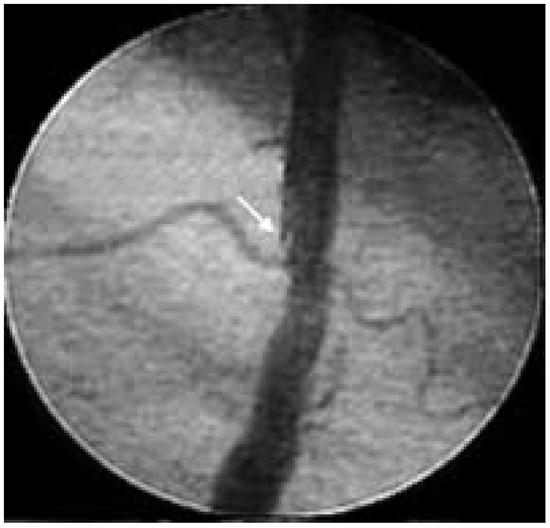

Diabetes leads to both micro- and macrovascular complications. If the major threat to type 2 diabetic patients is ischaemic heart disease, other cardiovascular complications such as heart failure, stroke and lower extremity arterial disease are also...